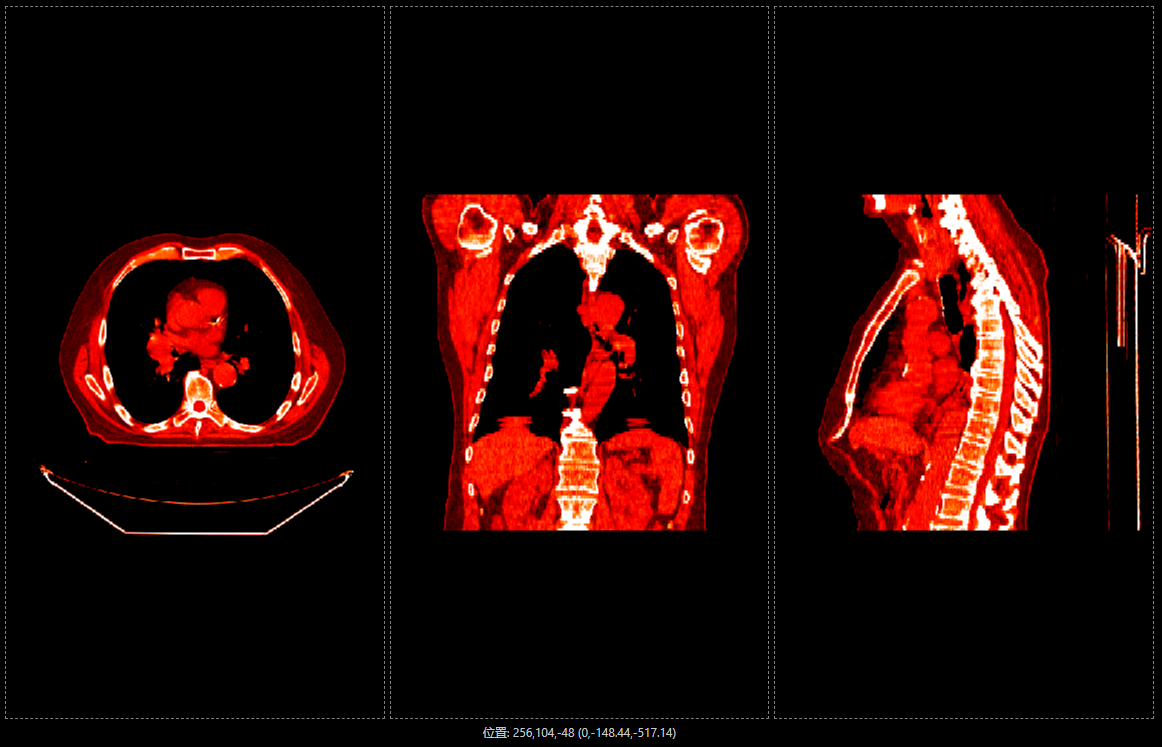

如果需要浏览样例的3D图像,点击工具箱里的“三维”按钮,等样例数据全部图片加载完成后即可查看。

3D图像界面:

伪色彩设置,即伪彩色映射,通过将灰度图像转换为彩色图像,有效地增强某些特征的可视性。它通过将灰度图像中的像素值映射到特定的颜色来实现彩色显示。医学影像中的灰度图经常用于表示不同密度或强度的区域,通过伪彩色映射,这些区域可以在视觉上更容易被识别和分析。DcmViewer 通过使用查找表(Look-Up Table, LUT)将每个灰度值映射到一个RGB颜色, 可以突出显示或隐藏不同的特征或信息,例如组织结构、病变位置或血管分布等。

DcmViewer 提供以下几种伪色彩设置下拉框 - Plain(白片), InvPlain (反片) ,Rainbow, Hot, Hot Iron, PET, Hot Metal Blue 和 PET 20 Step,根据DICOM规范标准,定义红、绿、蓝颜色查找表(Red Palette Color Lookup Table Data),将上述VOl(Value Of Interest)值通过颜色查找表(Red Palette Color Lookup Table Data)赋色。

如,选择Hot Iron的效果: